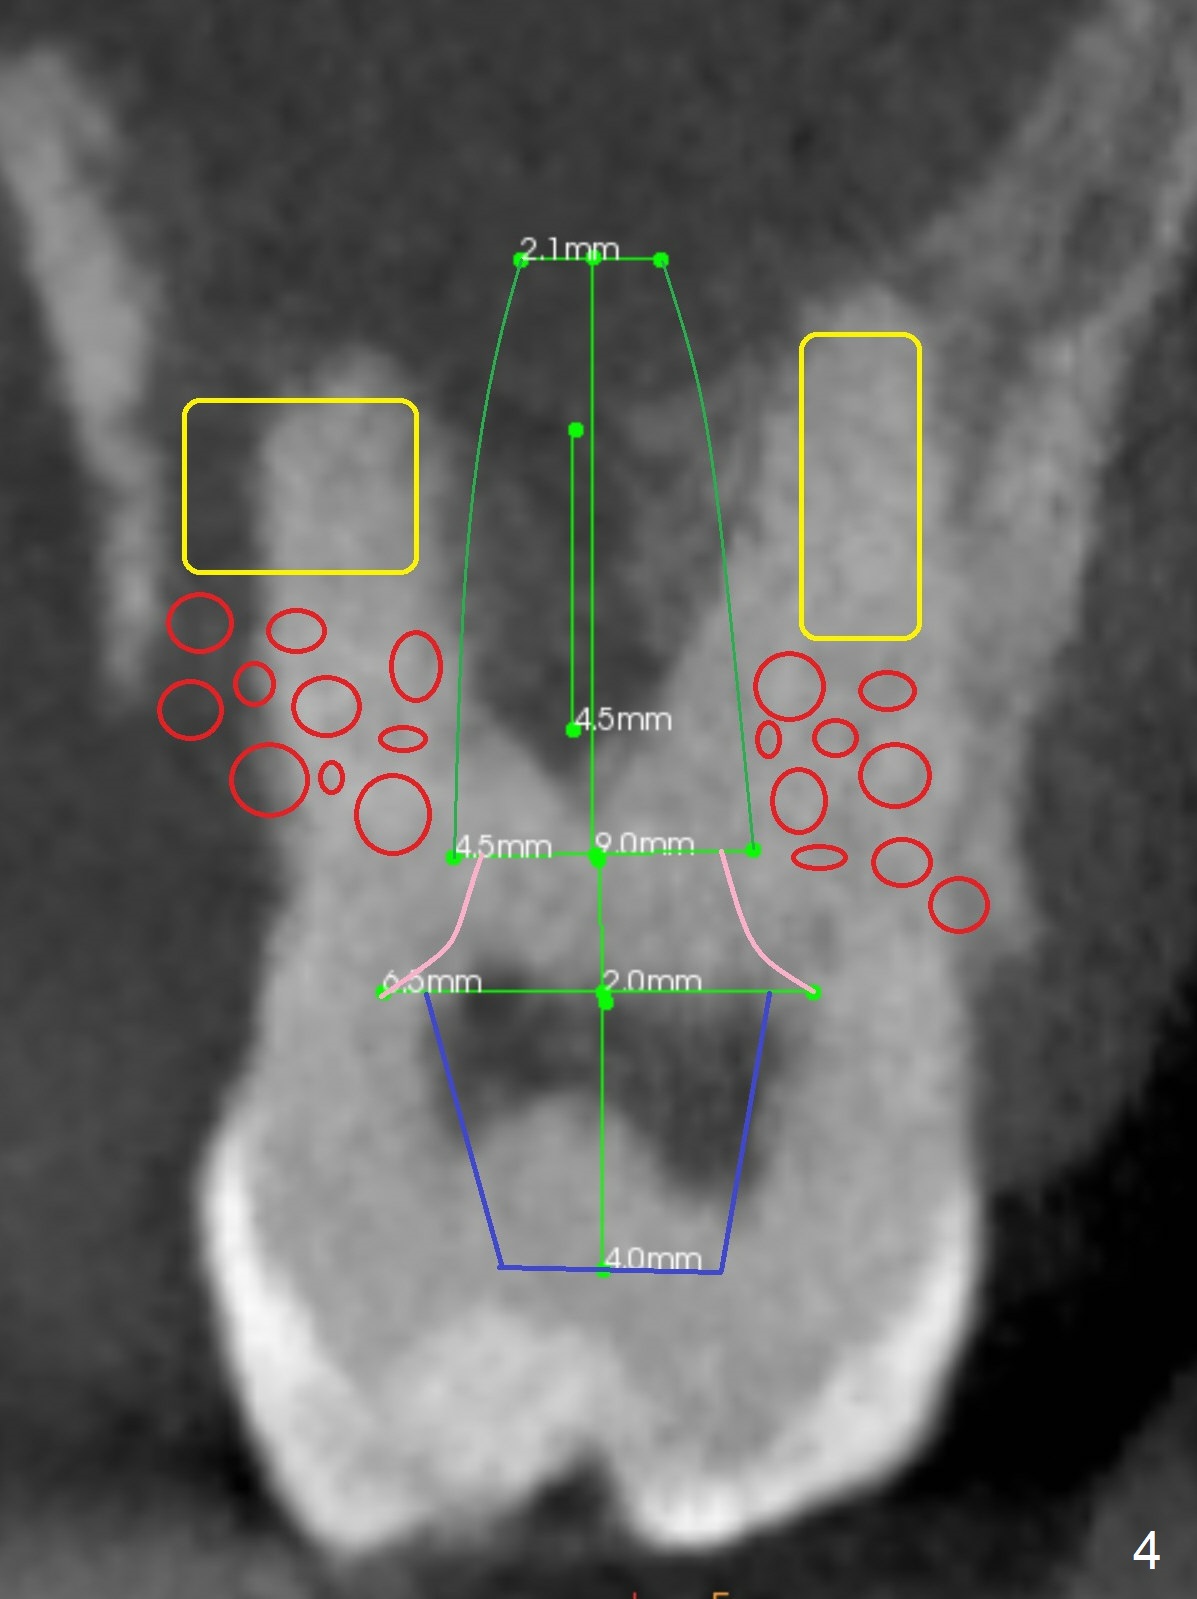

A 40-year-old man develops an abscess around the buccal roots of the tooth #15 several years after extraction of the symptomatic tooth #16. The pattern of infection is similar to that between #17 and 18. There is severe bone loss (Fig.1 *) around the fused buccal roots (Fig.2). It appears that an immediate implant (green) placed in the septum (Fig.4) has better position and angulation for restoration than the one placed in the palatal socket (Fig.3). Pink: cuff of abutment (blue); yellow: Osteogen Plug; red: bone graft.